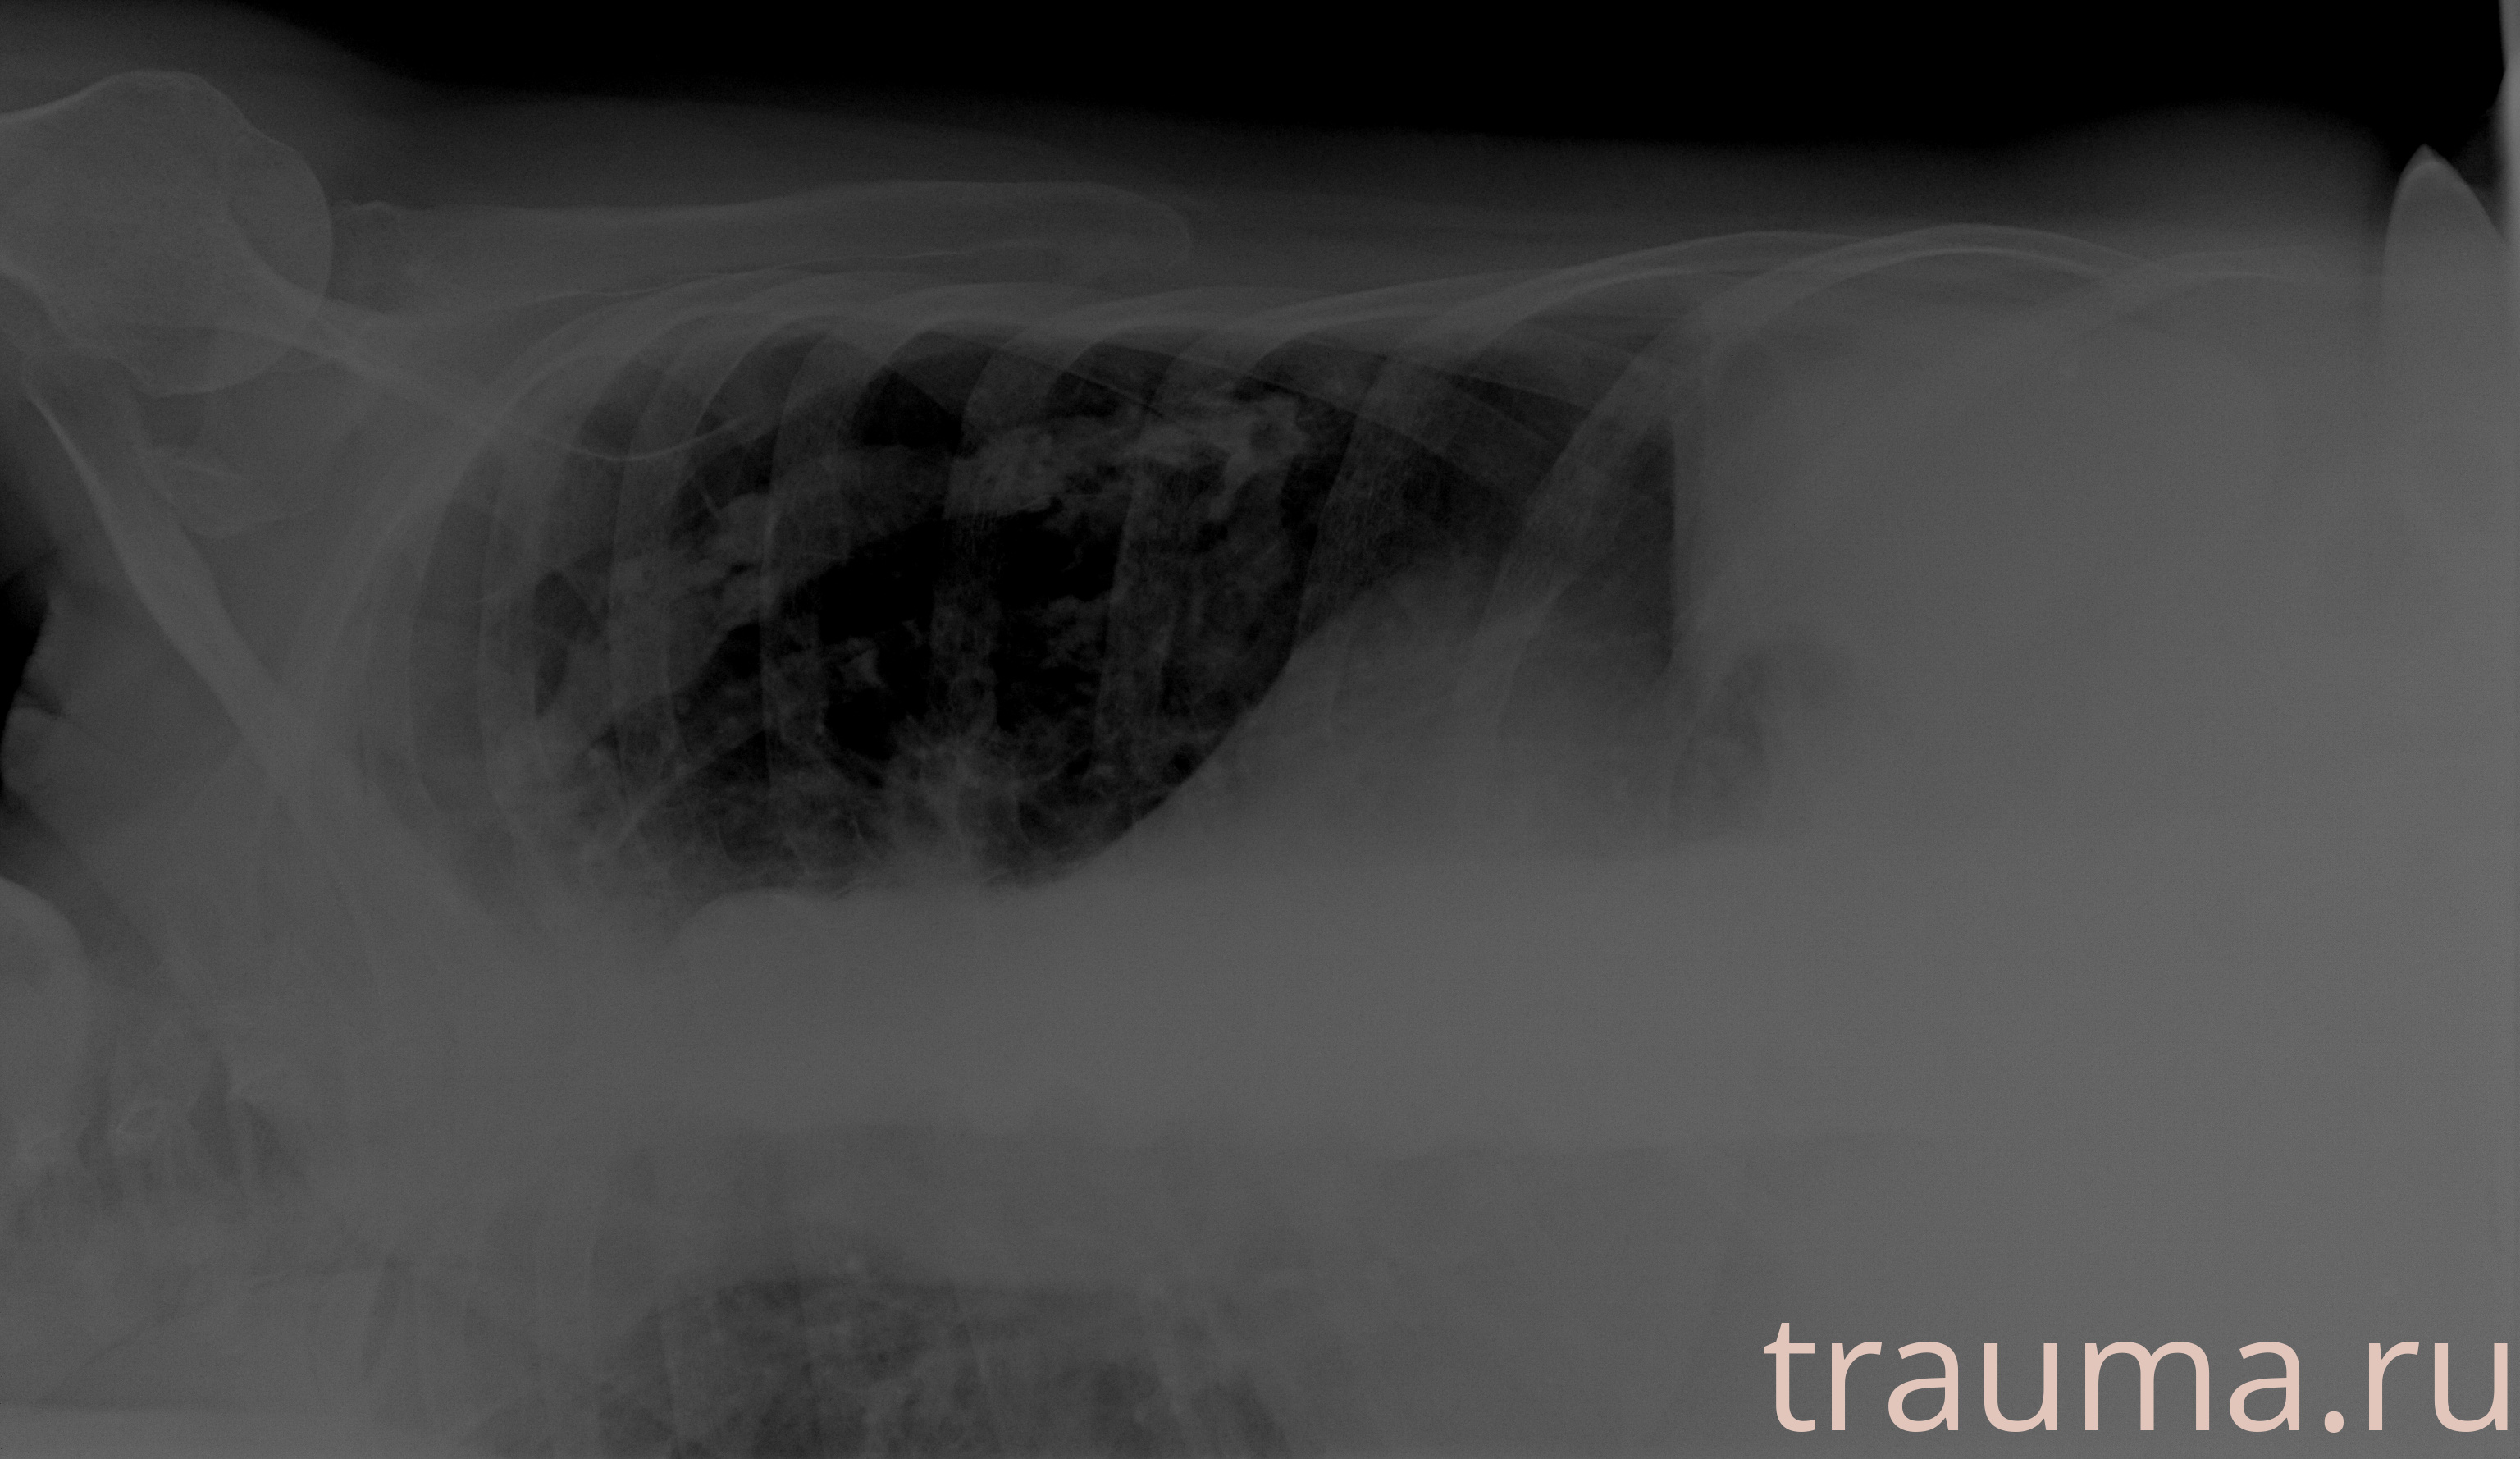

Рентгенограммы

Рентген на дому: по вашему адресу приезжает врач-рентгенолог, травматолог-ортопед с мобильным рентгеновским аппаратом, проводит диагностику травмы или заболевания, делает необходимые рентгенограммы, дает рекомендации по дальнейшему лечению. Получить качественные снимки в домашних условиях возможно благодаря уникальной методике, разработанной МосРентген Центром для института  Склифосовского

при переломе шейки бедра и пневмонии от компании МосРентген Центр - партнера Института имени Склифосовского